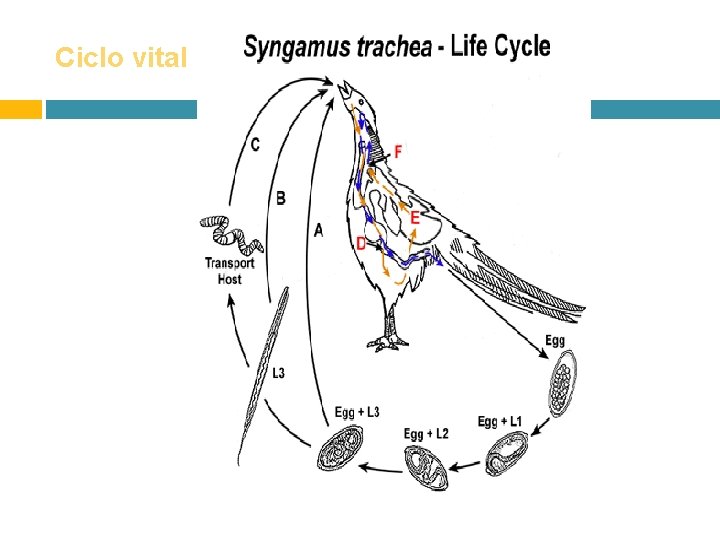

Ciclo vital